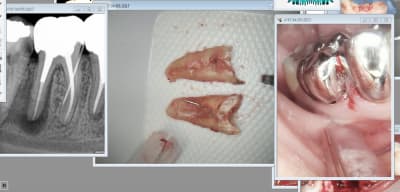

Tiens tout frais tout chaud, S1 gold, dévrillé, tordu, cassé. Pour la récupération je verrai la prochaine fois.

> Tiens tout frais tout chaud, S1 gold, dévrillé, tordu, cassé. Pour la

> récupération je verrai la prochaine fois.

> > Tiens tout frais tout chaud, S1 gold, dévrillé, tordu, cassé. Pour la

> > récupération je verrai la prochaine fois.

Nan c'est pas ça, doux comme les roubignoles d'un nouveau-né le vulpi. Nan que j'te dis, j'aurais dû passer une lime k manuellement avant, y avait un piège, suis tombé dedans, le problème des urgences en surnuméraire. Une fois j'ais mis un SX sur un CA bague bleu et zou 40 000 tr/min l'urgence... la galère.

> Tiens tout frais tout chaud, S1 gold, dévrillé, tordu, cassé. Pour la

> récupération je verrai la prochaine fois.

Avec les PT golds ce dont il faut tenir compte c'est de la morpho de racine. Sur une racine en huit, c'était le cas hier, tu passes large dans la grande boucle et puis sur le passage suivant tu choppes la petite boucle qui est peu (pas) préparée, effet de surprise+ blocage, ça casse.

Pour les racine longues, les canine, il faut tenir compte de l'effet de gainage et avancer à pas comptés, dans ces cas j'aime bien utiliser le moteur de l'unit et augmenter la vitesse de rotation progressivement, je trouve que l'on ressent bien ce qui se passe au niveau de l’instrument, c'est un des défauts du moteur gold, le ressenti est faible.